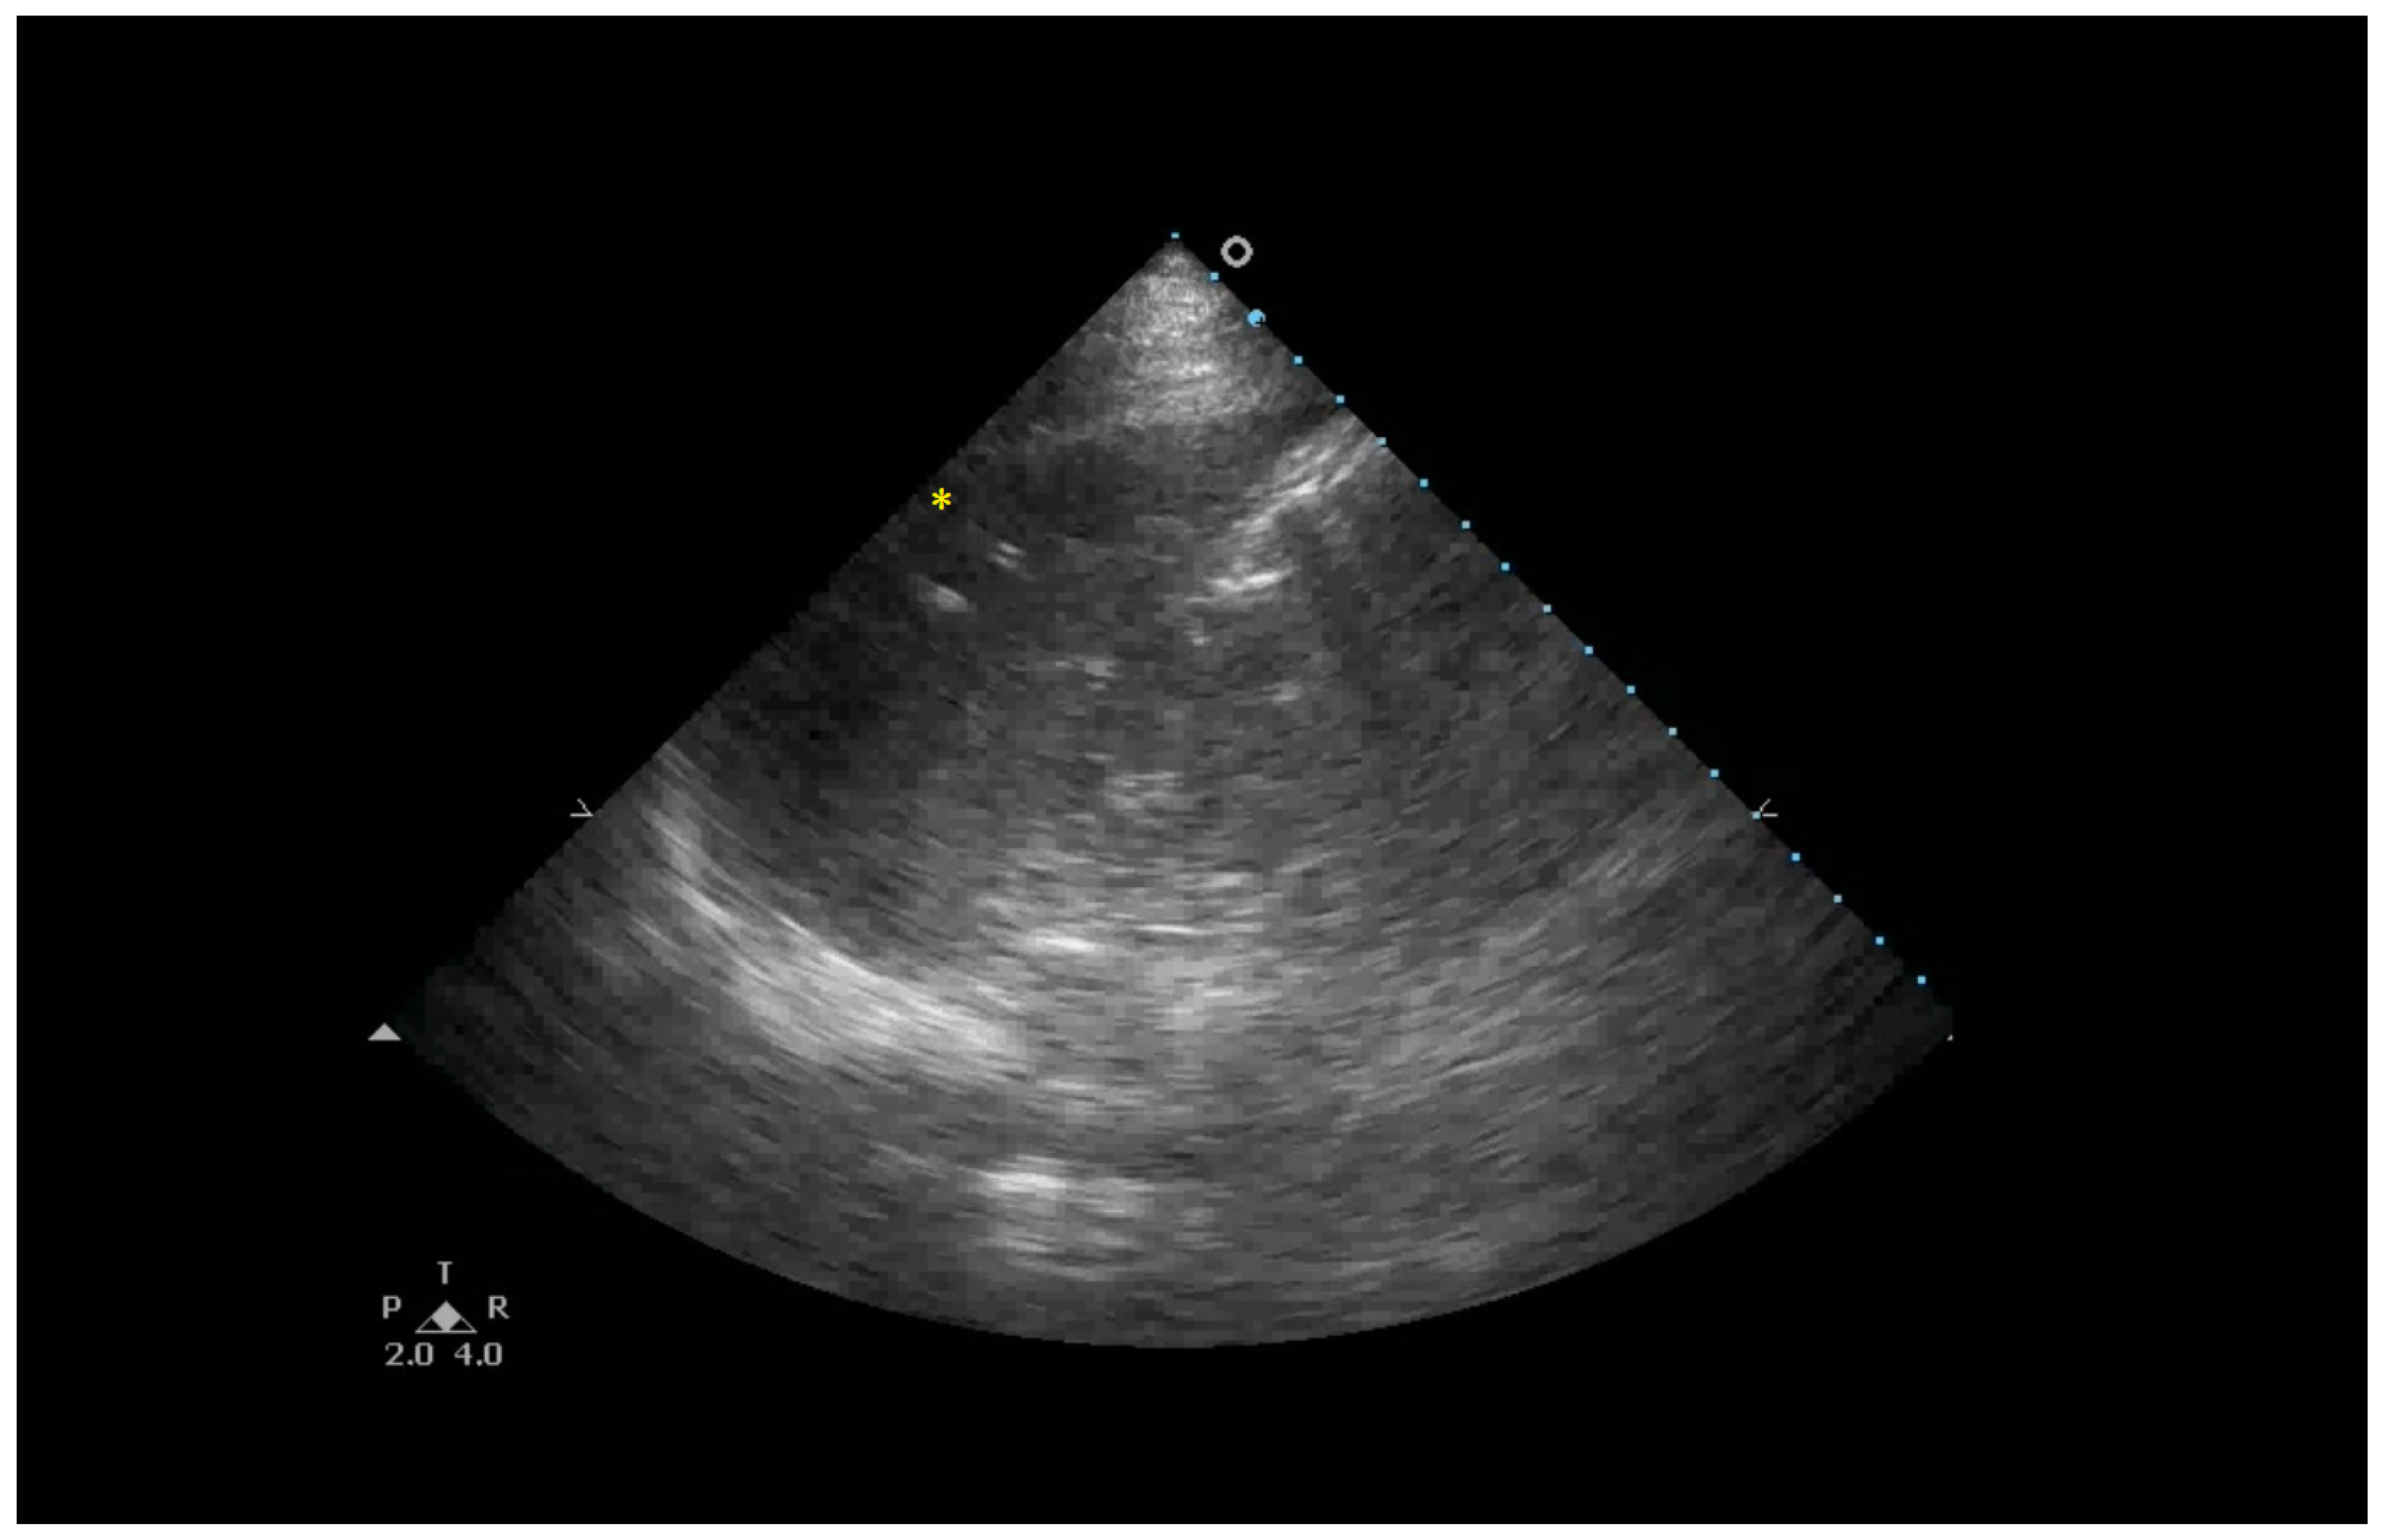

Figure 5.

Consolidations with an LUS score of 3 indicate a complete loss of aeration in the entire inferior right lobe (yellow *).

The following supporting information can be downloaded at https://www.mdpi.com/article/10.3390/healthcare13101148/s1, Clip S1: B-lines are hyperechoic artifacts descending from the pleural line to the bottom of the screen (yellow *); Clip S2: Multiple B-lines and irregular pleural line (yellow * and yellow ↓); Clip S3: Subpleural consolidation (yellow ↓) “Shred sign”; Clip S4: Consolidations with an LUS score of 3 indicate a complete loss of aeration measuring greater than 2 cm (yellow *). In addition, the preservation of the vasculature can be detected by color Doppler. Clip S5: Consolidations with an LUS score of 3 indicate a complete loss of aeration of the entire inferior right lobe (yellow *).